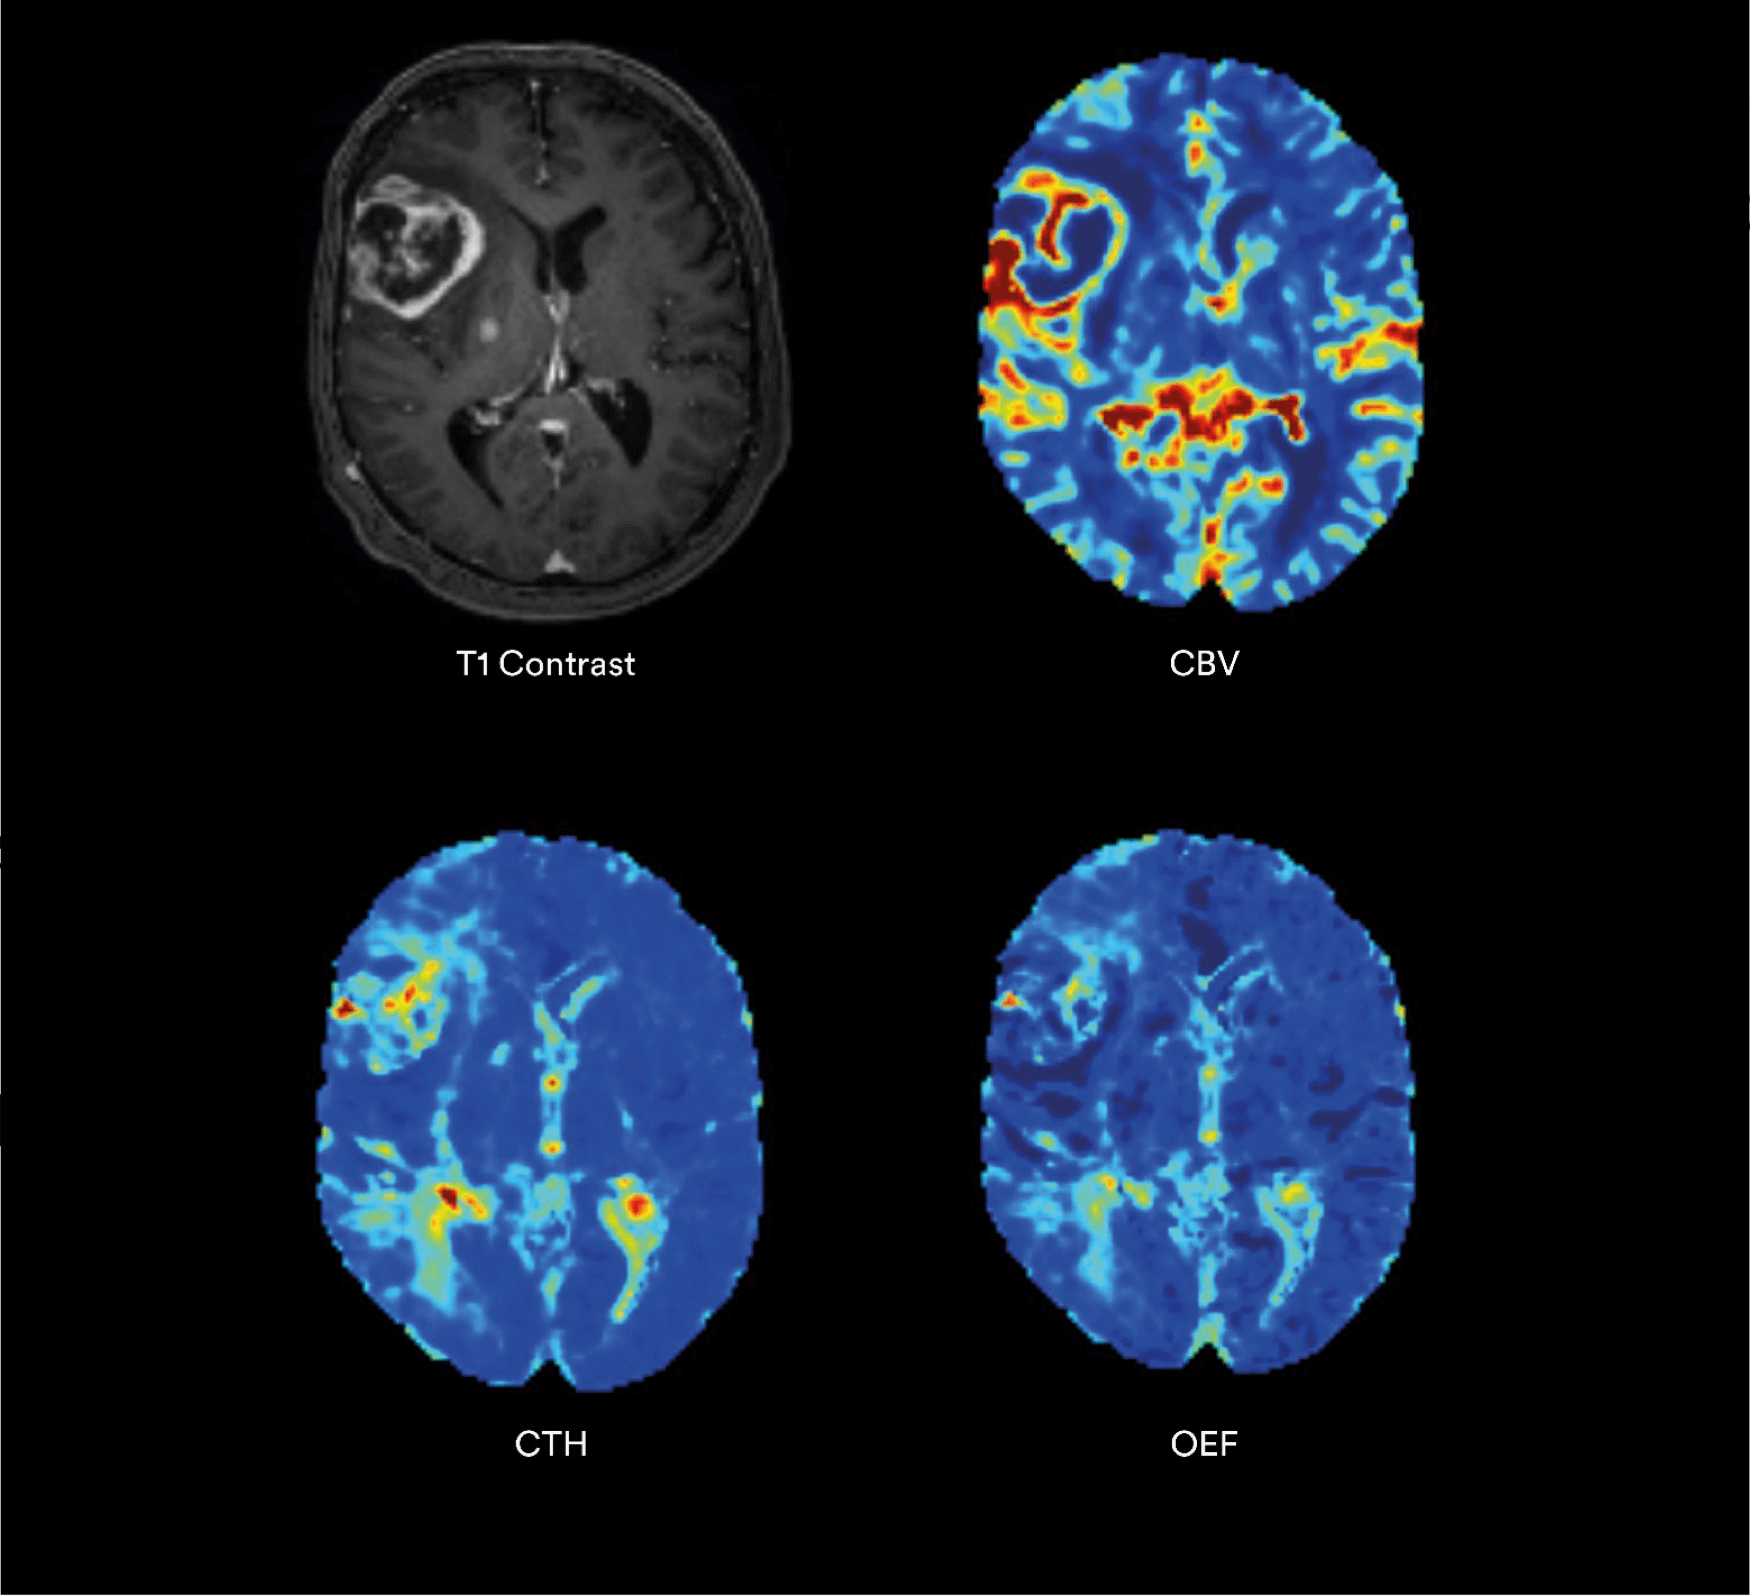

ONCOLOGY - Advanced Metabolic and Perfusion Imaging

In brain cancer, accurate lesion characterization is essential to determine aggressiveness, treatment, and prognosis.

PROPRIETARY BIOMARKERS FOR NEURO-ONCOLOGY

Vascular Biomarkers

- CTH Capillary Transit Time Heterogeneity.

- COV Microvascular Coefficient of Variance.

- Leakage Blood-Brain Barrier Integrity.